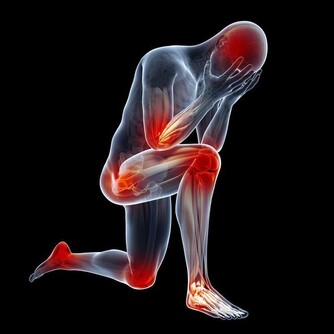

小貼士:大腸癌的症狀、便秘、腹瀉反復發生;

有血便和便血;糞便細;腹部有腫塊;

總感覺排便沒有排完全;腹痛;有貧血症狀。